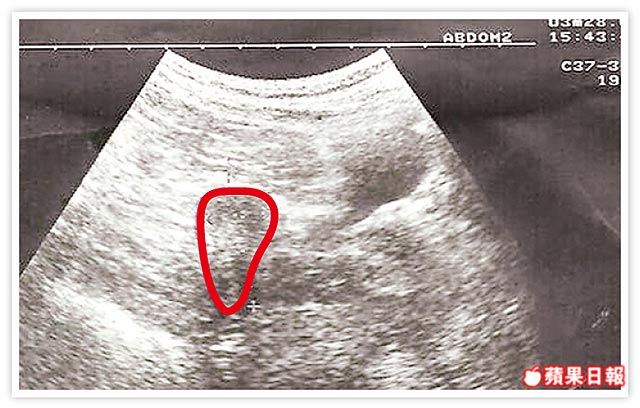

嚴重的卵巢過度刺激症候群: 7 年不孕 , 多囊性卵巢症候群 ...2013.09.03

她不孕症1.年紀32歲 2.做人工授精五次失敗 3.不孕症七年  ...2013.09.03

子宮小如櫻桃小丸子 Co 60 ...